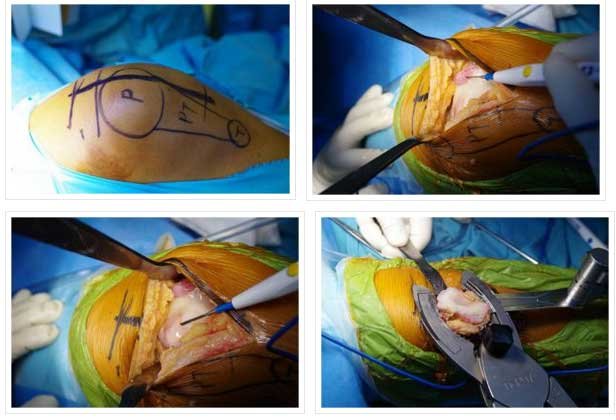

- 30 TO 45 MIN SURGERY

- UNDER TOURNIQUET AND NO DRAIN REQUIRED SO MINIMAL BLOOD LOSS (

- POSTOP EPIDURAL ANALGESIA

- NEXT DAY MOVEMENT TO START

- THIRD DAY DISCHARGE

- TOTAL RECOVERY IN TWO TO THREE MONTHS TIME

PATELLOFEMORAL

- PATELLA REPLACED WITH POLYTHYLENE INSERT

- TROCHLEA WITH UNCONSTRAINED METAL

- INLAY AND ONLAY TECHNIQUE: INLAY MY PREFERRED- LAZY

- PATELLAR TRACKING TO BE CLOSELY EXAMINED BEFORE SURGERY, MOST REQUIRE LATERAL RELEASE.